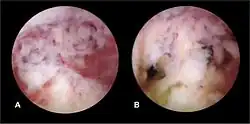

The history of a pregnancy event followed by a D&C leading to secondary amenorrhea or hypomenorrhea is typical. Hysteroscopy is the gold standard for diagnosis.[18] Imaging by sonohysterography or hysterosalpingography will reveal the extent of the scar formation. Ultrasound is not a reliable method of diagnosing Asherman's Syndrome. Hormone studies show normal levels consistent with reproductive function.

Fertility may sometimes be restored by the removal of adhesions, depending on the severity of the initial trauma and other individual patient factors. Operative hysteroscopy is used for visual inspection of the uterine cavity during adhesion dissection (adhesiolysis). However, hysteroscopy is yet to become a routine gynaecological procedure and only 15% of US gynecologists perform office hysteroscopy.[32] Adhesion dissection can be technically difficult and must be performed with care to not create new scars and further exacerbate the condition. In more severe cases, adjunctive measures such as laparoscopy are used in conjunction with hysteroscopy as a protective measure against uterine perforation. Microscissors are usually used to cut adhesions. Electrocauterization is not recommended.[33]